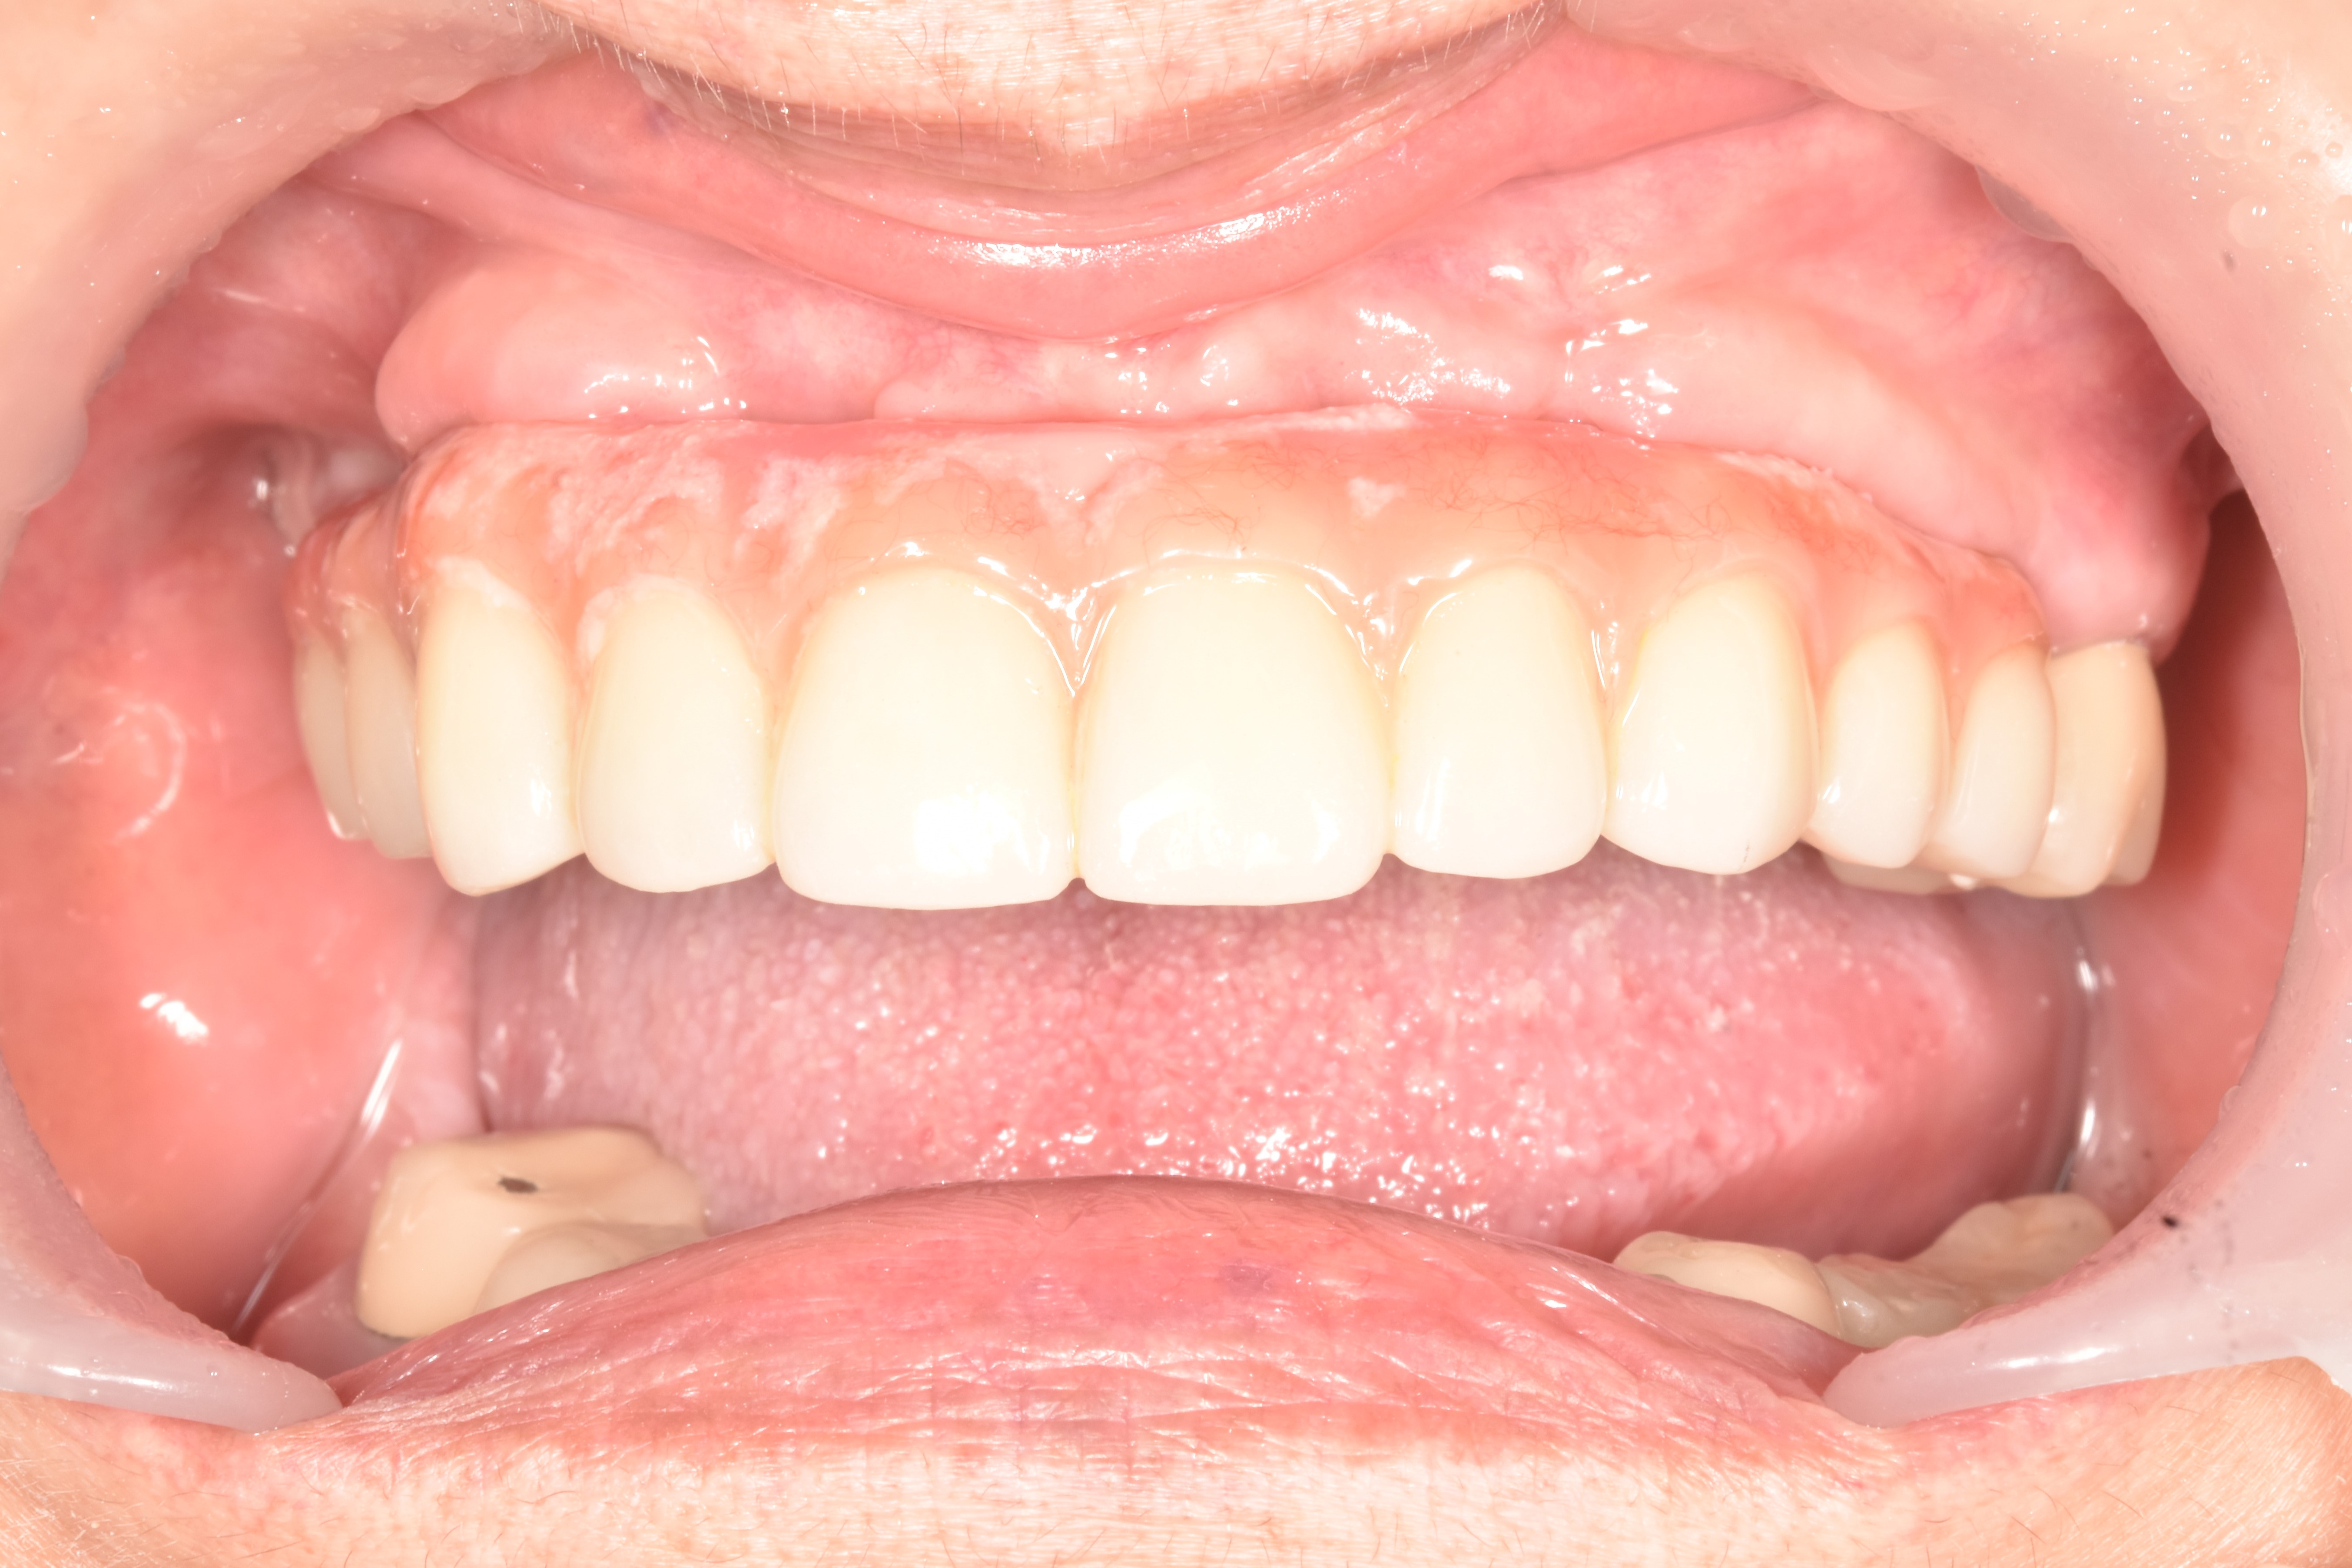

前牙美學植牙